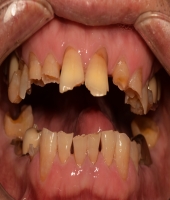

| ● 진료과목 : [임플란트] 치주환자의 보철치료

| ● 내용 : 60대 치주환자의 보철치료 |